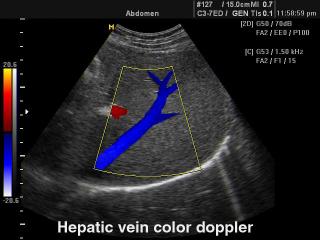

- CFM - цветное допплеровское картирование;

Конвексный датчик C 3-7ED/50/70

Акушерские исследования (плод, сердце плода), гинекология (матка, яичники), абдоминальные исследования (печень, желчный пузырь, поджелудочная железа, селезенка, глубокие сосуды), почки.

Биопсийный набор: есть.